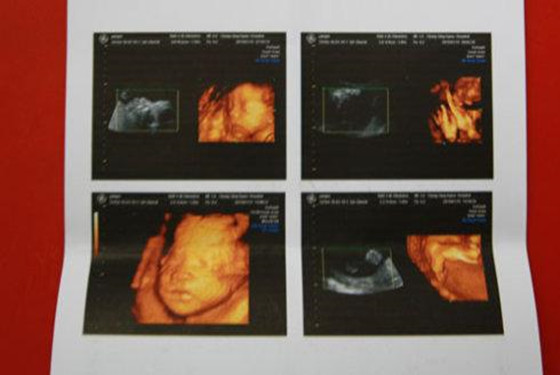

事实上,通过四维彩超是可以很直观立体的查看胎儿器官的,与普通B超相比四维彩超有更高的分辨率,对于胎儿的外生殖器官的辨认会更准确无误,很容易从彩超图中看出区别的。只不过,医院有规定医生即便是知道,也不会直接泄露胎儿的性别。熟一点的医生也只是间接性的提示一下,并不敢直接的告诉你怀的是男孩还是女孩的。这里想要强调的是为了避免误差,建议在怀孕24-28周时做胎儿肢体及脏器方面的检查,虽然怀孕16周时也可以看出胎儿性别,但是它并不是最佳的时机。

@YUHI221:四维彩超肯定能清楚的看出孩子的生殖器,只是医生不说罢了。我一个做医生的朋友透露过,女孩的生殖器图片为三条线,而男孩的生殖器图片好像蘑菇一样是凸起来的。